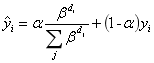

疾病分类的包含较多主观因素,存在较大噪声,训练不太稳定,选择轻模型多折训练以期提高稳定性。最终采用的MobileNet v3,三折训练。并做标签平滑,根据标签距离都给与非0真值,如标注标签是v2,离v1、v3都比较近,都给v1、v3的真值0.08,离v4比较远,给v4的真值0.008,剩下0.85就是标注标签v2的真值。

2.5.2 根据距离做标签平滑

v1-v4的标签用0-3的整数表示,设标注的标签真值为L,

第i个分类到标注标签的距离:

各分类的真值设置为: